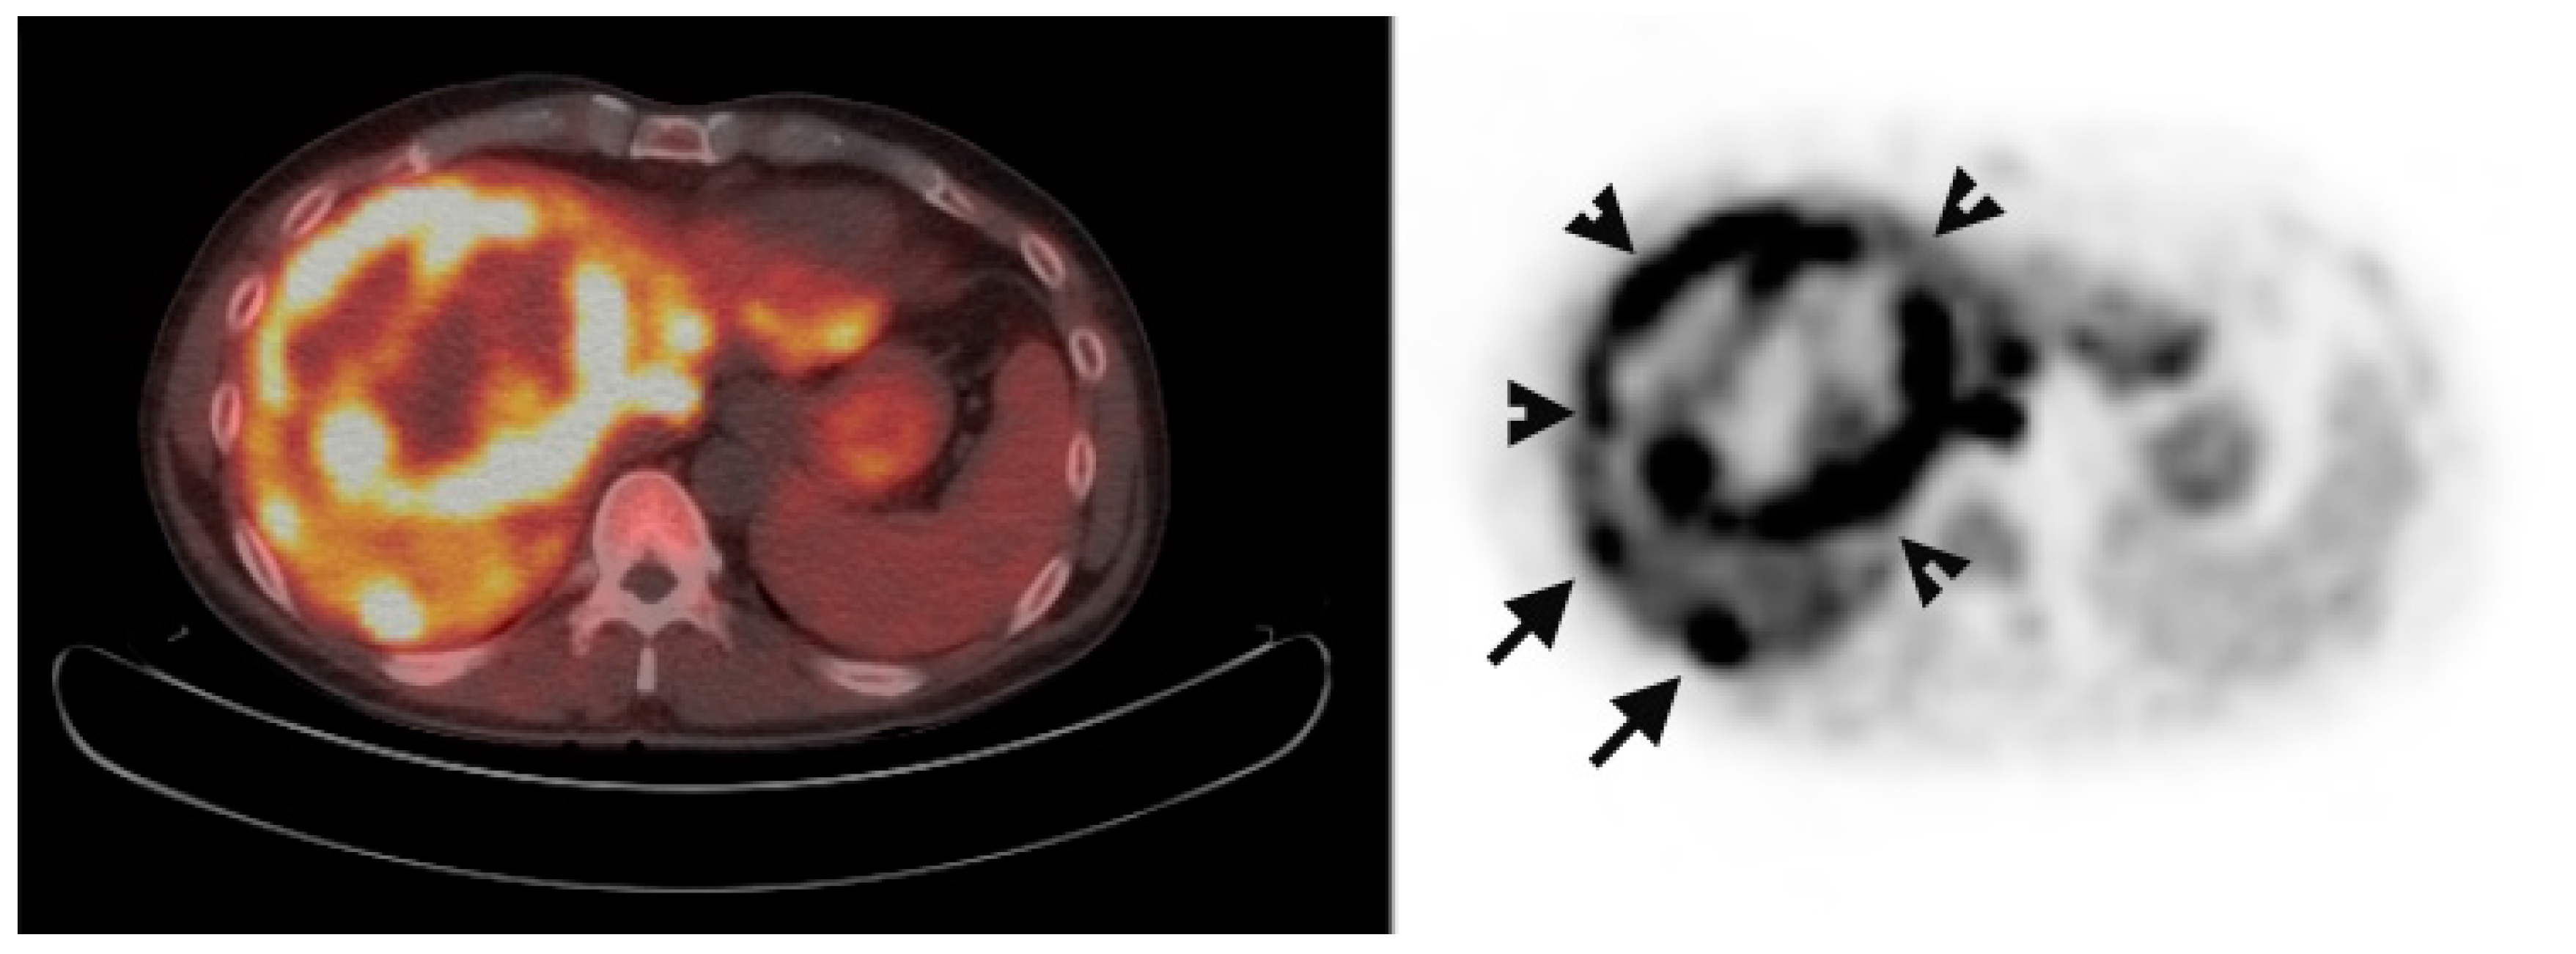

Multiple foci of increased FCh uptake in the liver consistent with multifocal or multinodular HCC (example, Figure 1) were noted in 8 of the 13 patients with increased primary tumor uptake. Of these, the areas of increased FCh uptake were adjacent to the treatment site (examples, Figure 2 and Figure 3) in 2 patients treated by local tumor ablation and 1 patient treated by liver resection. In one newly diagnosed case, PET demonstrated heterogeneous tumor FCh uptake with increased peripheral uptake and markedly diminished central uptake (Figure 4). Pathology in this case revealed a highly-necrotic tumor with Edmondson-Steiner grade 3 differentiation.

Figure 4.

Metabolic heterogeneity in HCC. Corresponding PET/CT (left) and PET (right) shows a heterogeneous region of increased uptake within the liver in this patient with newly diagnosed liver mass. Two small satellite tumors (arrows) are adjacent to the dominant mass (arrowheads surround). Histologically, this was a poorly differentiated HCC tumor.

This study shows that primary HCC can demonstrate a broad range of SUV values. This raises the possibility that FCh uptake is reflecting some phenotype of the tumor. Although a low TBR was encountered in a well-differentiated tumor (shown in Figure 7), other well-differentiated HCC tumors have been reported to show very high FCh uptake [16]. Clinical-translational studies involving tissue genomics or metabolomics could help to ascertain the molecular basis for these variations in tumoral and hepatic FCh uptake and potentially uncover novel biomarker applications in HCC.